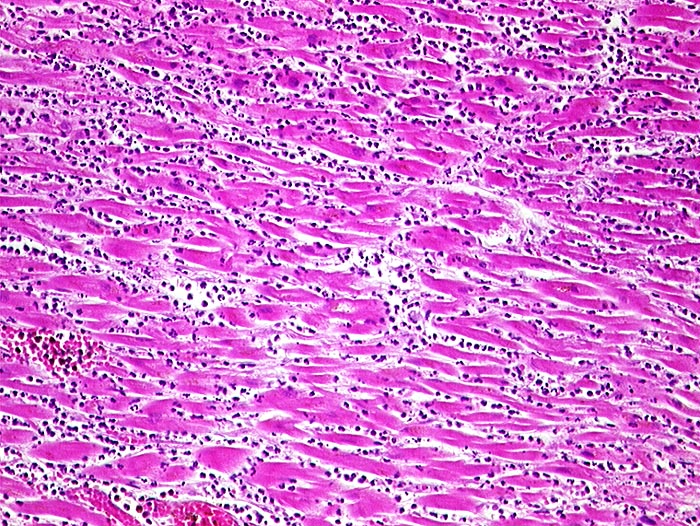

Nekrotische Myokardfasern ohne erkennbare Kerne. Dichtes granulozytäres Infiltrat.

Paninfarkt bei schwer stenosierender Koronarsklerose mit Abgangstenose beider Hauptäste. Alter Verschluss der Arteria coronaria dextra.

Zelluläre Infiltrate sind nach minimal 3 Stunden sichtbar. Kontraktionsbänder entstehen, wenn das hypoxisch geschädigte Myokard sich noch kontrahiert, aber nicht mehr relaxieren kann.